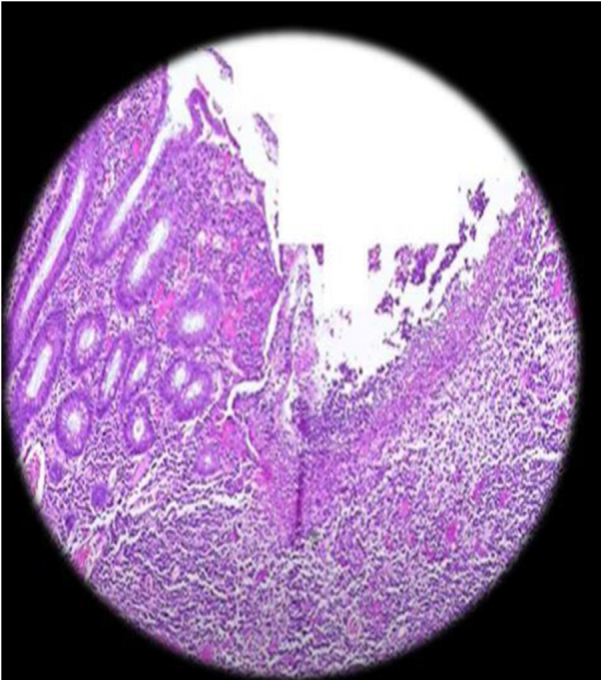

Case presentation: The patient presented with symptoms of abdominal pain, cramping, and significant bowel sounds, along with weight loss and a decreased appetite. Histopathological examination and upper endoscopy were used to diagnose the condition, and a gluten-free dietary treatment was implemented.

Clinical discussion: Crohn's disease can be diagnosed by several methods, including histopathology, and its treatment can involve various approaches, including dietary management. There is a connection with genetic diseases, and it is not necessary for all symptoms and signs of the disease to appear, as they often vary.